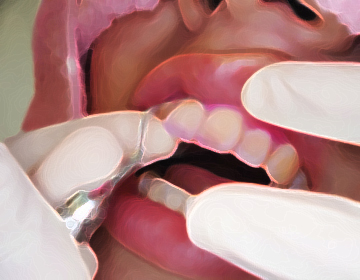

メインテナンスでは、お口の状態から日々のストレス状態を確認し、不調部位について歯だけではなく、

全身の健康状態維持のための養生法を含めた健康管理をお話いたします。

歯の状態と日々の生活環境から、ストレスや歯と全身にかかる負担を確認。

ハンドスケーラーを用いて、歯石とバイオフィルムを確実に除去します。

ジェット状の歯を痛めない特殊な粉で歯面の細かい汚れを取り除きます。

フッ素を含んだ研磨剤で歯の表面を研磨します。

虫歯などをチェックし、フッ素塗布後健康管理指導を行います。